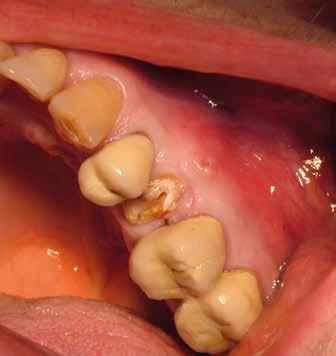

Alla visita di rivalutazione è emerso un ulteriore peggioramento della situazione, confermata anche dall’esame radiografico, con parodontopatia, sanguinamento al sondaggio, infiammazione diffusa, alitosi, difetto parodontale verticale mesiale a 2.3, residui radicolari 1.4, 1.6, 1.7, 3.6, 3.8 e carie destruenti di 1.5, 2.6, 3.5, 3.7 (con lesione endoperio) e 4.7 con estrusione e carie (Figg. 1, 2)

Il paziente, un uomo di 67 anni, ha confermato l’anamnesi precedente, ossia di essere portatore di

molteplici patologie: sindrome metabolica in discreto compenso farmacologico (riferita assunzione di metformina 500 mg, enalapril, acido acetilsalicilico, atorvastatina) e in terapia sostitutiva con levotiroxina perché operato di tiroidectomia totale per un tumore in giovane età; deambulazione autonoma con aiuto del bastone per via di un intervento al ginocchio abbastanza recente (riferito 6 mesi prima intervento di protesi totale di ginocchio).